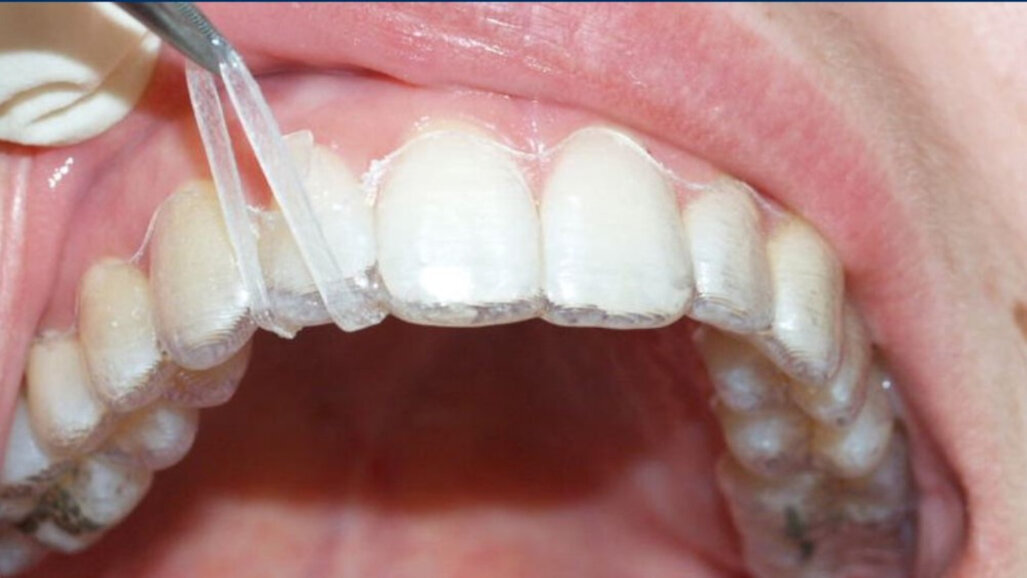

Aligners alone will fail because of the push that clear aligners produce, being very difficult to translate into the pull required to extrude teeth. Again, this is so despite brilliant attachments that incorporate inclined planes in attempts to overcome this limitation. Instead use fixed devices that will much more assuredly deliver extrusion. These can include buttons or elastics, intra- or inter-arch, or even fixed appliances first, transitioning to aligners alone once the extrusions have been produced (Figs. 4–9). The outcome is the delivery of true extrusion in a timely and effective manner early on and with less chance of aligner tracking loss.

Fig. 5: Intra-arch elastic–button technique.

Fig. 6: Extrusion elastic in place.